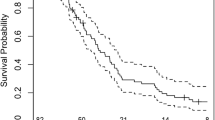

PFS in the long PPS group of the CCNU/TMZ arm was remarkably shorter as compared to the long PPS group of the TMZ arm (median 5.6 months vs 11.1 months, p = 0.01, Fig. 2A). Going in line with this, the mean PPS/PFS ratio tended to be higher in the long PPS group of the CCNU/TMZ as opposed to the long PPS group of the TMZ arm (7.7 vs. 4.5, p = 0.08, Fig. 2C). The PPS/PFS ratio was similarly low in the short PPS subgroups of TMZ and CCNU/TMZ arms with short PPS (1 vs. 1.1, p = 0.632).

Decreased progression-free survival and higher PPS/PFS ratio in long PPS CCNU/TMZ patients. Kaplan–Meier plots of patients followed TMZ or CCNU/TMZ therapy. Progression free survival (A) is given in patients from the modified intention to treat cohort of CeTeG/NOA-09 trial that had known PPS. Subdivision was made in short post progression survival (< 18 months) and long post progression survival (> 18 months) groups. Median PFS is remarkably low in CCNU/TMZ long PPS group compared to TMZ long PPS group (B), p = 0.01 (log-rank test). (C) Graph shows Mean PPF/PFS ratio of each subgroup

The combination of particularly low PFS with very long OS is prominently seen in the long PPS subgroup of the CCNU/TMZ arm. This raises the question whether at the time point of fulfilling the mRANO progression criteria, the underlying biology (e.g. contribution of pseudoprogression) in this subgroup may be different from the long PPS subgroup of the TMZ arm. We further investigated if these differences are also mirrored in MRI at mRANO-defined progression.